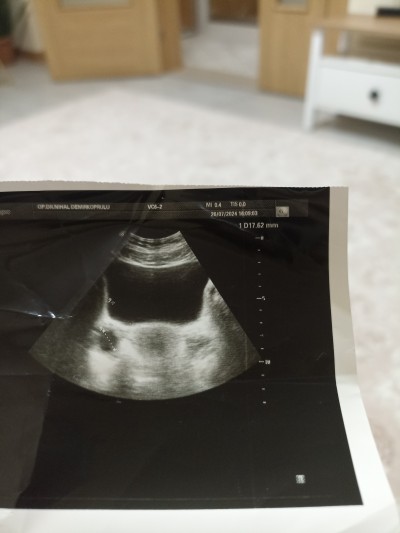

Sağ tarafta 17 mm yumurta oluşmuştu şimdi tekrar baktım da sol tarafta yumurta olabilir mi orada bir kasık ağrım var bu ay çatlatma ignesi oldum femara kullandım ağrı hep o tarafta neden acaba

image